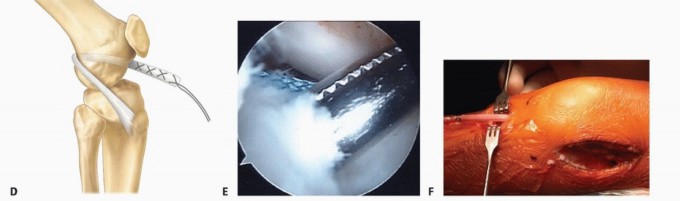

Through the lateral incision, the iliotibial band graft is sutured near the over-the-top position to the

intermuscular septum and the periosteum of the posterior lateral femoral condyle with the knee flexed 90 degrees, tension on the graft, and the foot externally rotated 30 degrees (

TECH FIG 3A

).

Fluoroscopic imaging is used to assess the location of the proximal tibial physis.

TECH FIG 3 • Graft fixation for physeal-sparing ACL reconstruction. A. With the knee flexed 90 degrees, tension on the graft, and the foot externally rotated 30 degrees, the graft is secured to the intermuscular septum and the periosteum of the posterior lateral femoral condyle near the over-the-top position. B. With the knee flexed to 20 degrees, the tensioned graft is secured to the periosteum at the roughened margins of a trough in the proximal tibia. Fluoroscopic imaging is used to ensure that the proximal tibial physis is not disturbed. (A: From Kocher MS, Weiss JM. ACL reconstruction in the skeletally immature patient. In: Tolo VT, Scaggs DL, eds. Master Techniques in Orthopaedic Surgery: Pediatrics. Philadelphia: Lippincott Williams & Wilkins, 2008:277-287.)

A longitudinal incision is made in the periosteum distal to the proximal tibial physis.

The edges are gently elevated and a trough is made in the proximal tibial medial metaphyseal cortex. The knee is flexed 20 degrees and tension applied to the graft.

The graft is sutured to the periosteum at the roughened margins with mattress sutures (

TECH FIG 3B

). The knee is checked for stability to Lachman testing and ROM.